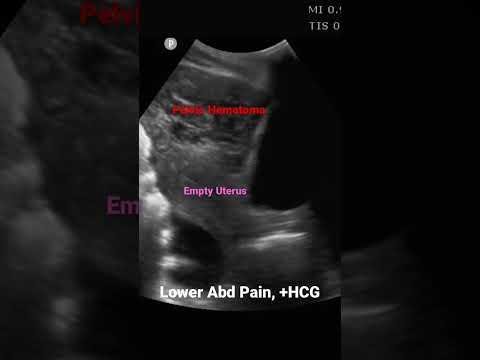

Rare Diaphragmatic Ectopic Pregnancy: Advanced Imaging Key for Diagnosis

In the medical field, cases of ectopic pregnancy often present…